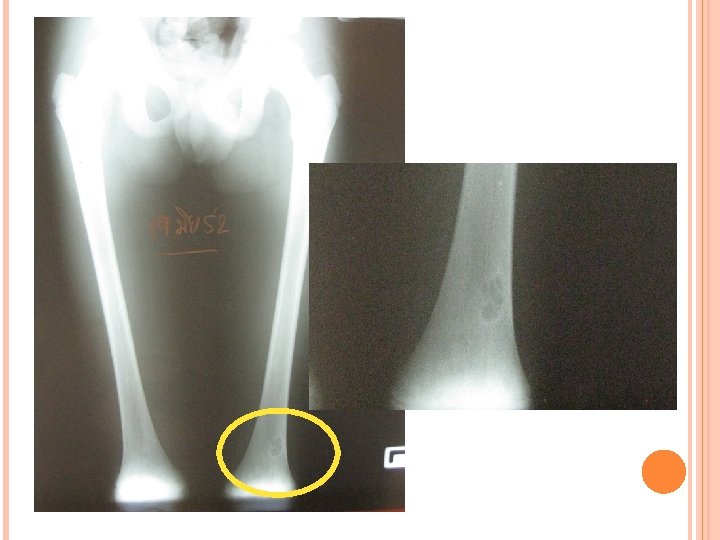

BMA: inadequate BM biopsy: fragment of cartilage, no bone marrow tissue seen Film bone survey: multiloculated cystic lesion at distal of Lt femur, no osteolytic lesion, suspected benign condition, No malignancy condition Bone scan: ? Ultrasound abdomen: hepatomegaly

Multiple radiolucency lesions